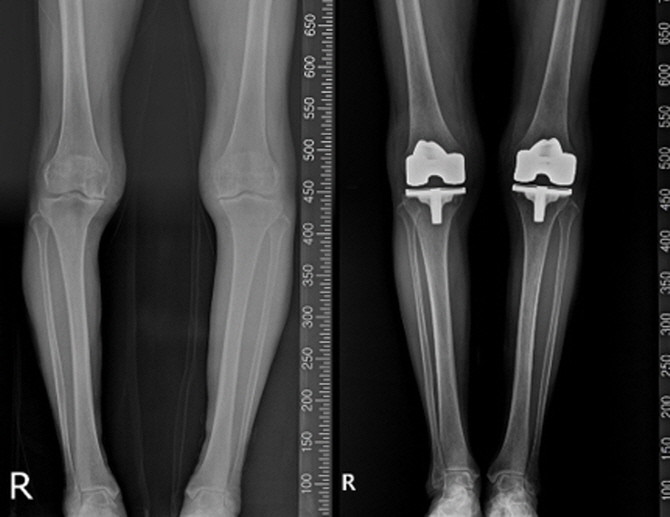

연세사랑병원은 MRI 및 영상 데이터를 활용한 '니비게이트' 플랫폼과 환자 맞춤형 수술 가이드(PSI)를 통해 수술 정확도를 높이고, 회복 속도와 장기 안정성을 개선하고 있다고 16일 밝혔다.

연세사랑병원에 따르면 니비게이트는 수술 전 환자의 MRI 및 영상 데이터를 기반으로 무릎 관절의 정렬, 뼈의 형태, 변형 정도를 정밀 분석해 수술 계획을 수립하는 플랫폼이다.

니비게이트 인공관절 수술의 핵심은 PSI(Patient Specific Instrument, 환자 맞춤형 수술 가이드)의 활용이다. PSI는 환자 개인의 해부학적 특성을 반영해 제작된 맞춤형 절삭 가이드로, 수술 중 뼈를 절삭하는 위치와 각도를 보다 정확하게 유도하는 역할을 한다. 이를 통해 기존 획일적인 수술 방식에서 벗어나 환자 개개인에 맞춘 정밀한 인공관절 삽입이 가능해진다.

고용곤 연세사랑병원장은 "퇴행성 관절염 환자는 같은 진단명이라도 관절 변형의 정도와 뼈의 형태가 모두 다르기 때문에 환자 맞춤형 수술이 중요하다"며 "니비게이트 플랫폼과 PSI를 활용한 인공관절 수술은 환자의 해부학적 특성을 정밀하게 반영해 보다 정확하고 체계적인 수술을 가능하게 하는 것이 특징"이라고 말했다.